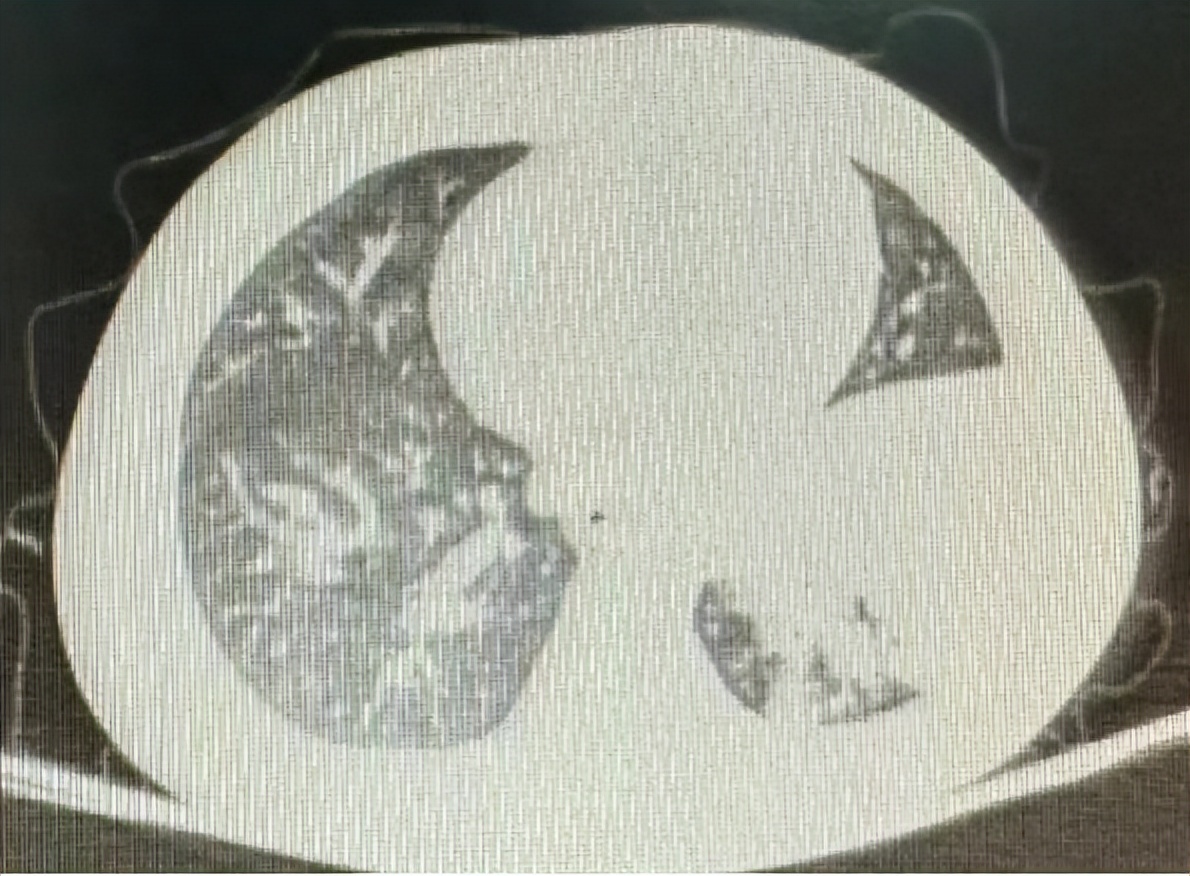

2岁男童,因“发热、咳嗽1周,加重1天”入院。院前曾查肺部CT提示左肺炎症,并在院前治疗5天,热不退,后又治疗3天,仍有高热,立即复查肺部CT示大叶性肺炎较前加重。

反复或持续的高热,咳嗽或不伴有咳嗽,肺部CT都显示出部分肺叶实变,这种波及各年龄段的大叶性肺炎,已引起我科门诊及住院部医生的特别注意。